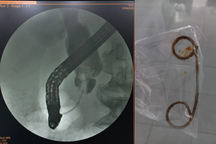

Stent dài 15cm bị bỏ quên trong ống mật chủ của bà T. khoảng 6 năm qua (Ảnh: Bệnh viện cung cấp).

Qua thăm khám, bác sĩ chẩn đoán bà T. bị tắc mật ngoài gan do nhiều sỏi ống mật chủ, nhiễm trùng đường mật do đặt stent bị bỏ quên trong ống mật chủ.

Trong hơn 90 phút, các bác sĩ phẫu thuật mổ hở để lấy sạch sỏi, stent bị bỏ quên trong ống mật chủ; đồng thời, xử lý tình trạng nhiễm trùng.